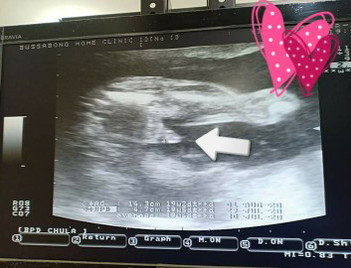

ด้วยความมั่นใจของคุณพ่อเค้า ได้อย่างใจเลยค่ะ ...คุณได้ลูกชาย อิแม่แอบหวังเล็กๆ อยากได้ผู้หญิงค่ะ บ้านอื่นลูกสาวหรือลูกชายค่ะ